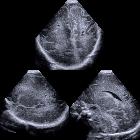

fetal intracranial cystic lesions

Fetal intracranial cystic lesions can arise from a number of pathologies, including: